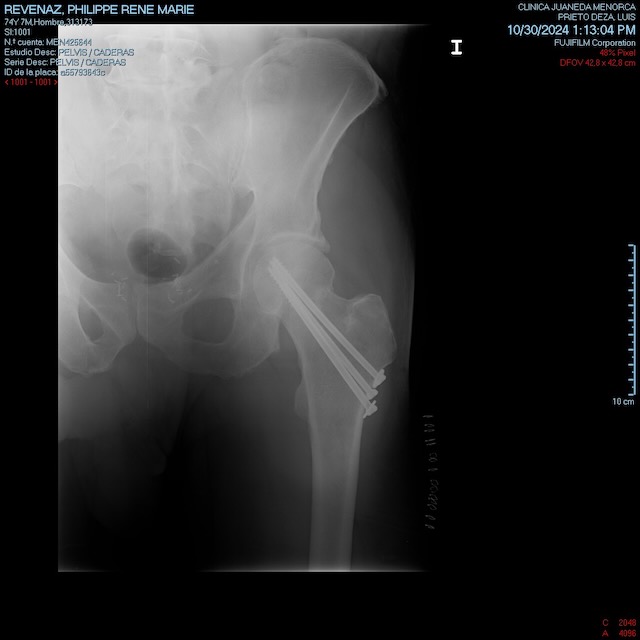

Mais ça ne passe pas…. alors tout s’enchaîne très vite: une visite aux urgences de l’hôpital Juaneda de Ciutadella, ultra moderne, une IRM, et oui le col du fémur est bien cassé, un tour au bloc dans la foulée, et voilà notre Pilou lesté de trois magnifiques vis en tungstène, deux béquilles et une petite chance de pouvoir reprendre le ski en mars, si tout se passe bien….????